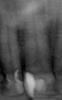

Hermit Опубликовано 26 января, 2008 Автор Поделиться Опубликовано 26 января, 2008 У верхушки корня может быть широкая разветвленная сеть мелких каналов отходящих от основного. И при лечении зубов под анестезией даже после хорошей обработки канала там остаются нервные клетки которые могут давать боли. И если для пломбирования канал применялась паста с слабыми антисептическими свойствами то можно сказать, что инфекция в этих микро-канальцах продолжает жить и беспокоить вас . Если ваш доктор отказывается лечить зуб, то обратитесь к заведующему отделению этой клиники, должны же они вам помочь, у вас же гарантия на этот зуб есть? Гарантия то есть, да нет желания видеть эту докторшу. Скорее всего, она мне вообще зря депульпировала этот зуб. Кроме того, у нее нет стратегии зубосохранения, а есть установка сделать "все правильно" - чтобы удалить нерв и запломбировать канал она мне так сильно расточила коронку, что от нее почти ничего не осталось. И пойду я к ней, и что она сделает? Что-нибудь такое, что и представить себе трудно. Время идет, а зуб все болит. Я ходил на консультации к разным другим врачам, и все они не видели ничего такого, что стоило бы перелечивать. Только недавно был еще у одного врача, у которого сделал новый снимок и который усмотрел на нем затемнение у верхушки того самого проблемного первого верхнего зуба. Считает, что надо перепломбировать. Я что думает форум? Если надо, то как лучше лечить? http://i008.radikal.ru/0801/5c/776daf7ebe60t.jpg Ссылка на комментарий

Doc Опубликовано 26 января, 2008 Поделиться Опубликовано 26 января, 2008 Гарантия то есть, да нет желания видеть эту докторшу. Скорее всего, она мне вообще зря депульпировала этот зуб. Кроме того, у нее нет стратегии зубосохранения, а есть установка сделать "все правильно" - чтобы удалить нерв и запломбировать канал она мне так сильно расточила коронку, что от нее почти ничего не осталось. И пойду я к ней, и что она сделает? Что-нибудь такое, что и представить себе трудно. Время идет, а зуб все болит. Я ходил на консультации к разным другим врачам, и все они не видели ничего такого, что стоило бы перелечивать. Только недавно был еще у одного врача, у которого сделал новый снимок и который усмотрел на нем затемнение у верхушки того самого проблемного первого верхнего зуба. Считает, что надо перепломбировать. Я что думает форум? Если надо, то как лучше лечить? http://i008.radikal.ru/0801/5c/776daf7ebe60t.jpg Ничего не знаю о личных качествах Вашего врача, но с виду эндодонтия сделана очень качественно. Ссылка на комментарий

Hermit Опубликовано 26 января, 2008 Автор Поделиться Опубликовано 26 января, 2008 Ничего не знаю о личных качествах Вашего врача, но с виду эндодонтия сделана очень качественно. Вот и все говорят качественно. Я и сам вижу. Но зуб то болит. Боль при надавливании. Особенно утром после сна. Потом немного сходит. Как-то мне по другому зубу ударили. Так вот ощущение сходное. Еще где-то под десной на миллиметр и ближе ко второму зубу что-то постоянно зудит. Так как насчет затемнения у верхушки? Оно что-то означает? Надо перепломбировать или как? Ссылка на комментарий

Doc Опубликовано 27 января, 2008 Поделиться Опубликовано 27 января, 2008 Вот и все говорят качественно. Я и сам вижу. Но зуб то болит. Боль при надавливании. Особенно утром после сна. Потом немного сходит. Как-то мне по другому зубу ударили. Так вот ощущение сходное. Еще где-то под десной на миллиметр и ближе ко второму зубу что-то постоянно зудит. Так как насчет затемнения у верхушки? Оно что-то означает? Надо перепломбировать или как? Снимок очень некачественный, возможно, что мне кажется, но в верхней трети нет ли трещины? Там как раз толщина пломбировки разная, видно глазом, вправо чуть выше и влево чуть ниже какая-то еле различимая линия. Возможно трещина. Хотя по этому снимку сложно сказать. Были какие-то удары, падения, укусы вилки или что-то такое? Ссылка на комментарий

Hermit Опубликовано 27 января, 2008 Автор Поделиться Опубликовано 27 января, 2008 (изменено) Снимок очень некачественный, возможно, что мне кажется, но в верхней трети нет ли трещины? Там как раз толщина пломбировки разная, видно глазом, вправо чуть выше и влево чуть ниже какая-то еле различимая линия. Возможно трещина. Хотя по этому снимку сложно сказать. Были какие-то удары, падения, укусы вилки или что-то такое? Снимок делался на визиографе, но там он почему-то смотрелся лучше, хотя только переформатировал его в jpg. В тот день делался еще один снимок, который пошел в брак, но ствол корня на нем виден. Там линий нет, а то что пломбировка утончается на трети, это факт. Не падал и не ударялся, вилки не грызу. Не помню в ближайшем прошлом что-то такое, что могло его травмировать. Он заболел первоначально очень странно. Утром просыпась и чувствую, что на него больно нажимать и как будто вокруг него воспалено внутри десны. У меня до сих пор подозрение, что это не нерв болел. http://i045.radikal.ru/0801/be/6929d8377cbet.jpg может я ошибаюсь, но от форфенана зуб краснеет, изменяет цвет. разве можно им каналы пломбировать во фронтальном отделе? Наверное Вы ошиблись А при постукивании по зубу боль есть? Если на холод реагирует зуб то это где то рядом зуб болит, а отдает в депульпированный. Или остаточный пульпит. Может и ошибся. Так в калькуляции написано. Одной графой гуттаперча, другой - форфенан. На постукивания и на холод реагирует очень слабо. Больше когда на него нажимаешь или давишь в стороны. Но, главное, сам по себе постоянно ноет. Первый левый рядом с ним - мертвый со школьных времен, второй правый пришлось умертвить, пока разбирался с этим злополучным первым правым. Если остаточный пульпит, то что делать? Так мне не кто и не сказал, что-то значит затемнение у верхушки корны или нет? Изменено 27 января, 2008 пользователем Hermit Ссылка на комментарий